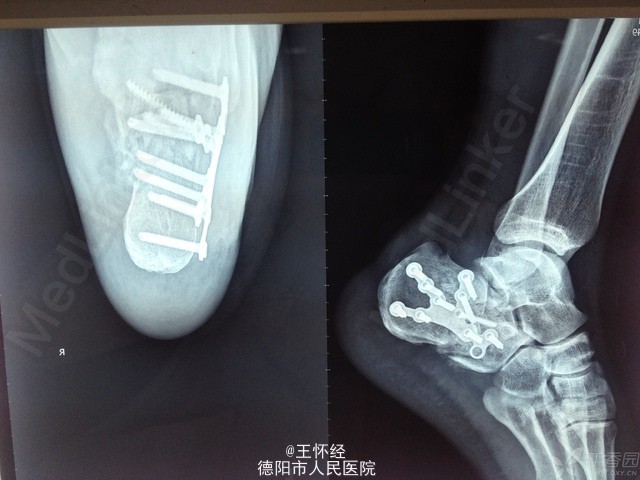

跟骨骨折

患者男性,49岁,车祸伤导致跟骨骨折,入院后完善常规检查,急诊手术。